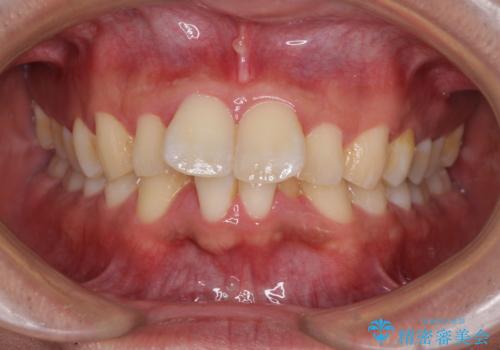

- 前歯や奥歯の虫歯を放置しており、それらの治療を契機に真っ白な歯にしたいとのことで来院された患者様です。

不自然なくらい真っ白にしたいとのことでしたので、透明感のないフルジルコニアクラウンを用いて補綴することとしました。